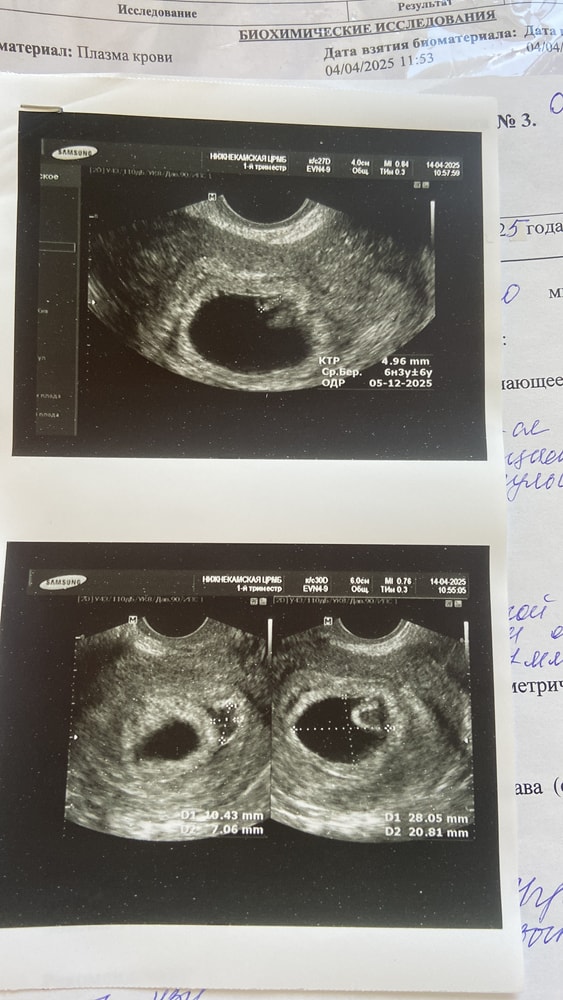

Лежала на сохранении, так как 14 апреля по узи сказали что есть отслойка. 18 апреля сделали узи, сказали Эмбриональный срок 4-5 недель. Эмбрион растет. 14 апреля эмбрион был 6,3, а вчера 18 апреля эмбрион уже 9.

думаю просто рано они делают выводы. Слышала что у многих сердцебиение только в 8-9 недель прослушивается. И если была бы не развивающаяся беременность, я так понимаю то эмбрион бы и не рос?

узи за 14 апреля и 18 апреля прикрепляю.

Идите СРОЧНО к другому платному узисту. У вас на первом УЗИ написано ктр 4.96 мм, а в заключении врач пишет 6,3 мм. Где он взял эти данные, если аппарат прописал другую информацию.